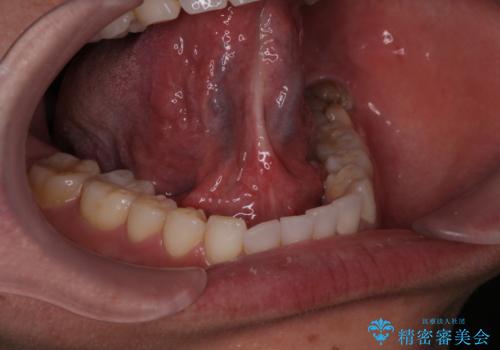

- 滑舌が悪く舌小帯を切りたいとの事で来院。

舌小帯切除術を行いまいした。

1週間後に抜糸をして終了です。